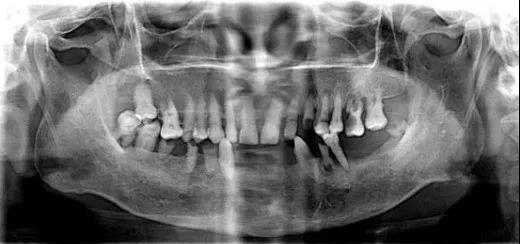

马先生的牙齿情况

与47岁的马先生相反的是,另外一位同时完成种植牙手术直播的患者。

王叔叔前牙缺失,无法正常吃饭

在进食的过程中,王叔叔松动的牙齿被硌松掉,牙缝也越来越大,门牙的情况岌岌可危。

王叔叔的前牙松动

长期缺牙导致严重的牙周疾病,让两位患者长期饱受缺牙的痛苦,吃不好饭,生活也被影响。